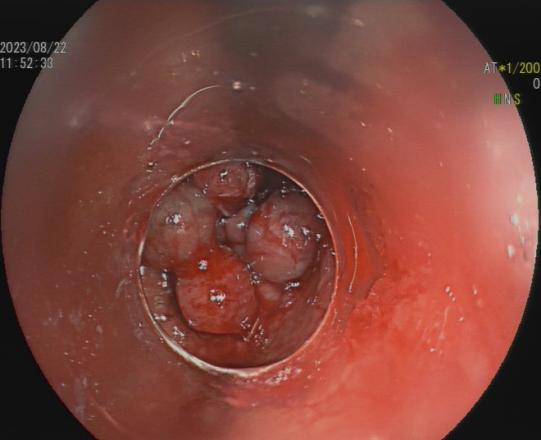

三、早期消化道肿瘤ESD技术

内镜下粘膜剥离术(ESD),具有超级微创、安全性高、住院时间短及费用低等优势。

直肠巨大绒毛状腺瘤 内镜下粘膜剥离过程

粘膜剥离术后创面 剥离的巨大腺瘤